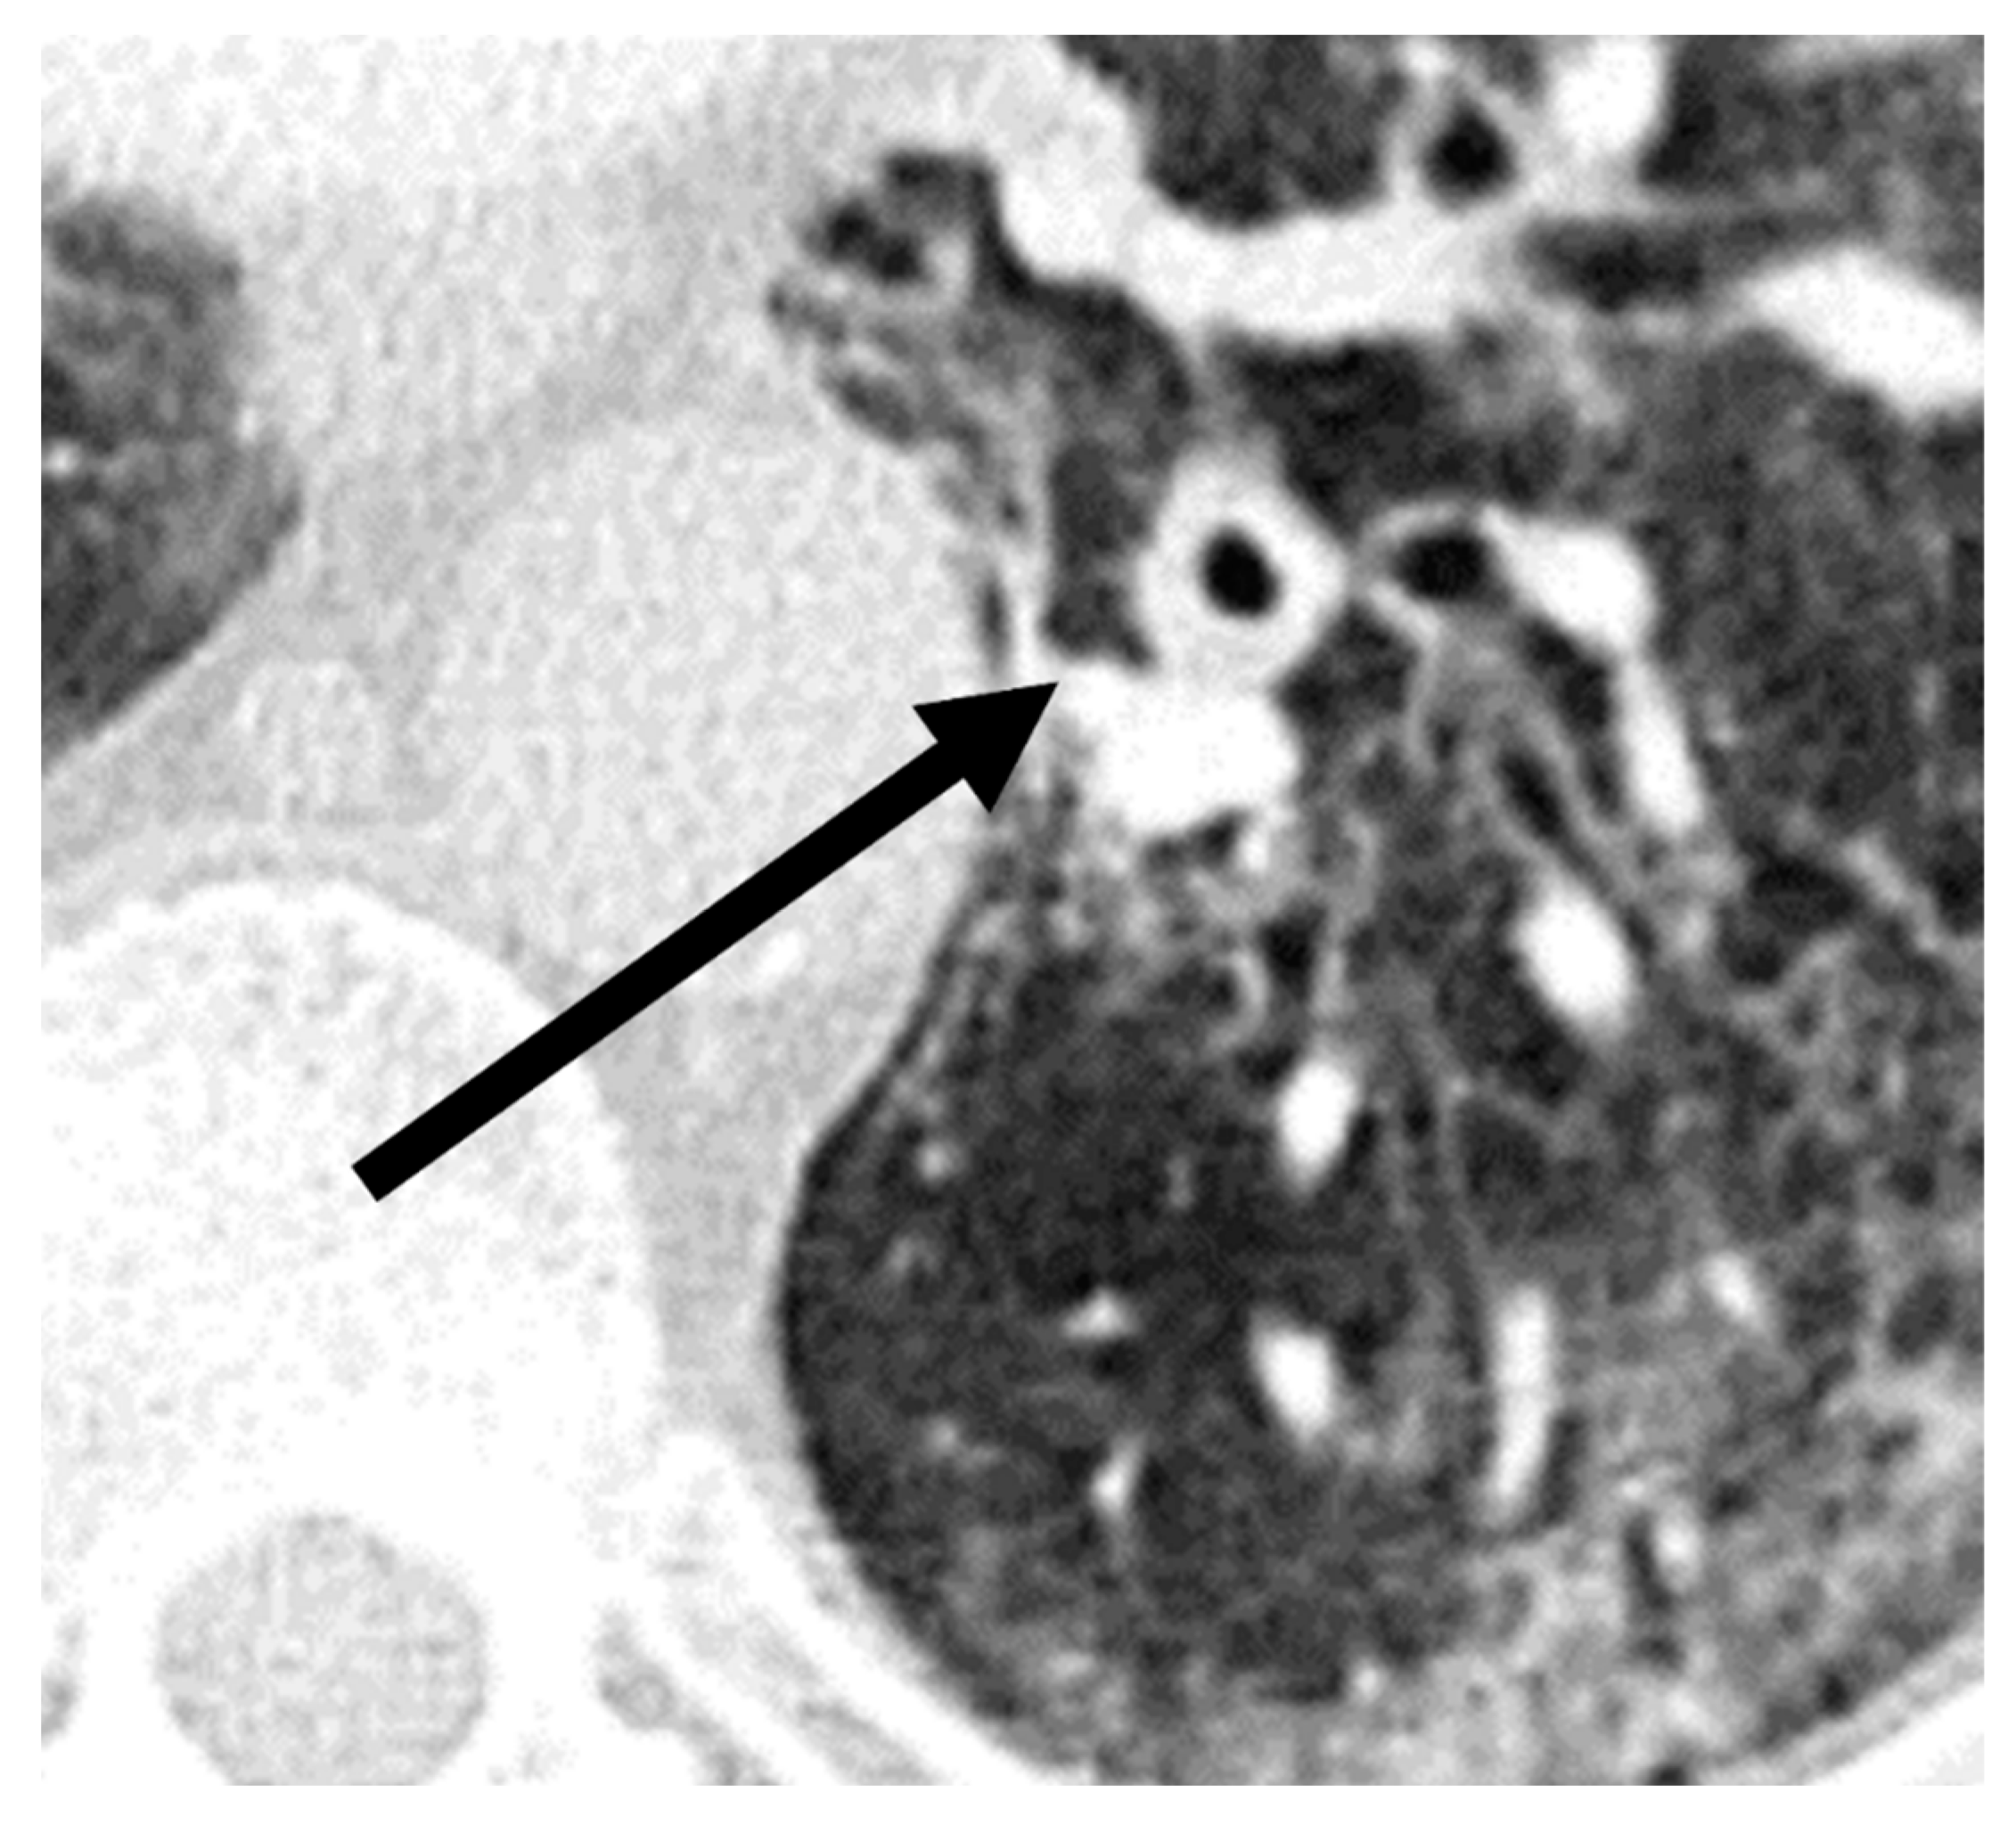

A comparison of additional findings between patients with COVID-19 and with CAPA (Table 2) indicated that bronchial wall thickening (p = 0.03) was observed more often in the CAPA group. Representative images of chest CTs of a patient with CAPA are shown in Figure 3.

Figure 3.

Imaging example of bronchial wall thickening (arrow) in a patient with probable COVID-19-associated pulmonary aspergillosis (CAPA). CT was performed 10 days after symptom onset on the day of the CAPA diagnosis. The T/D ratio (wall thickness (T) divided by the total diameter of bronchus (D)) was 0.32 in this case.